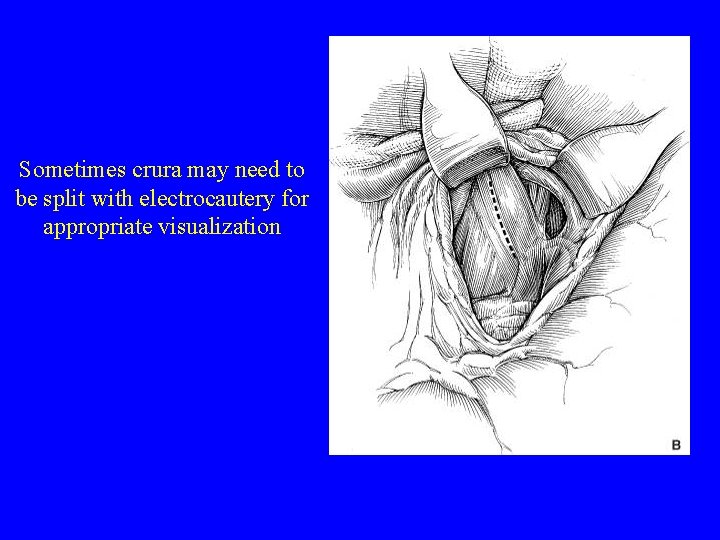

Sometimes crura may need to be split with electrocautery for appropriate visualization